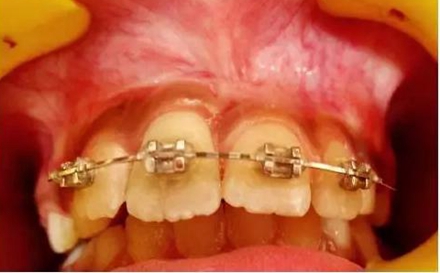

正畸牽引觀察其復位情況: 先觀察挫入的牙齒在未干預的情況下自發(fā)復位的情況。經過3周的觀察,牙12復位,但牙11沒有顯示出復位的跡象。因此,使用MBT托槽正畸牽引牙11復位。為了讓其沿正確的方向復位,使用橡皮圈以獲得緩慢持續(xù)的牽引力(圖3)。

(圖3)

正畸牽引5周后,牙齒復位到其原始位置,與其他切牙完全對齊(圖3)。開始嘗試血運重建。重新打開根管,使用次氯酸鈉和生理鹽水沖洗。然后插入無菌根管銼,并將其推到根尖處,以使血流進入根管。一旦血液到達釉牙骨質界,放置一個濕潤的無菌棉球靜置15分鐘,直到血凝塊形成,再放置約2-3mm的MAT在血凝塊上。在MAT上覆蓋一個濕棉球,隨后進行臨時修復。以后再替換為玻璃離子水門汀墊底和復合樹脂修復。復診時間為1、3、6、9和12月。正畸復位保留12周。然而,在這么長的保留期內還是復發(fā)了錯位,這也強調了在嚴重侵入的情況下長期復位的重要性,因為累及的牙齒周圍出現(xiàn)大量的牙槽骨喪失(圖 4)。